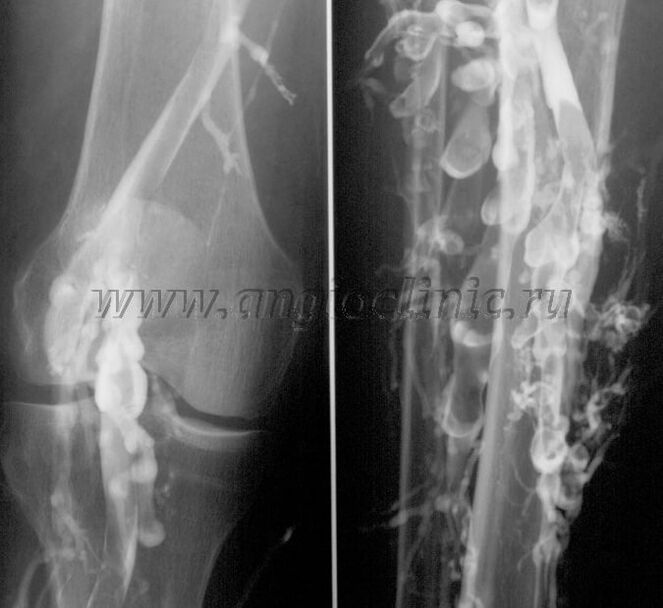

Контрастна венография

Обикновено ултразвуковото сканиране е достатъчно за пълна диагностика на венозна патология, но в някои случаи е необходимо да се изследва връзката между състоянието на дълбоката и повърхностната венозна система, особено при рецидиви на разширени вени и вторични разширени вени.

За решаването на тези проблеми се използва контрастно рентгеново изследване. Сафенозните вени се пунктират и се прилага контраст. Движението на контраста се наблюдава на монитора на рентгеновия апарат и се извършват всички необходими изследвания и проекции. В момента венографията за разширени вени се използва много рядко.